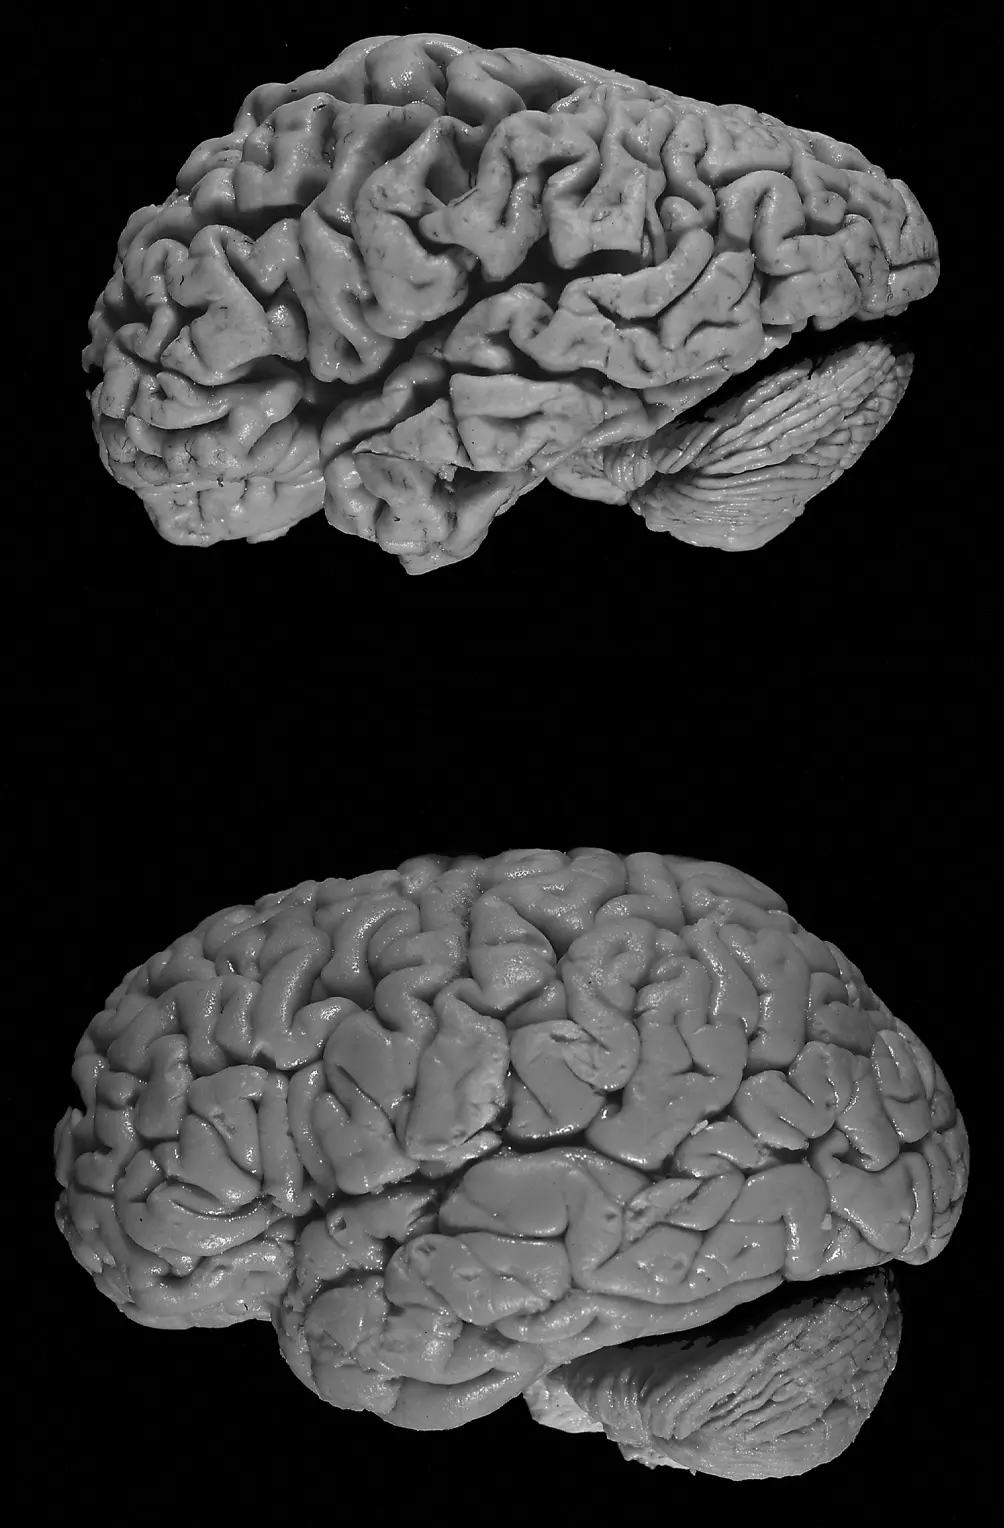

Die Schwangerschaft ist eine Zeit voller Veränderungen, sowohl physischer als auch emotionaler. Eine oft diskutierte Frage ist, ob sich das Gehirn während der Schwangerschaft verändert und ob diese Veränderungen dauerhaft sind. Die einfache Antwort ist: Ja, das Gehirn schrumpft während der Schwangerschaft. Aber keine Angst, dieser schrumpf ist nicht unbedingt ein Zeichen von Gehirnschaden oder Demenz. Er ist vielmehr ein natürlicher Prozess, der dem Körper hilft, sich auf die Herausforderungen der Mutterschaft vorzubereiten.

Der Begriff gehirn schrumpft klingt zunächst beängstigend, aber es ist wichtig, ihn im richtigen Kontext zu verstehen. Es bedeutet nicht, dass das Gehirn einfach verschwindet. Vielmehr bezieht sich dieser Ausdruck auf eine Reduktion des Gehirnvolu mens, die während der Schwangerschaft stattfindet. Diese Reduktion betrifft hauptsächlich die graue Substanz, die für höhere kognitive Funktionen wie Gedächtnis, Sprache und Entscheidungsfindung zuständig ist.

Es ist wichtig zu betonen, dass diese Reduktion des Gehirnvolu nicht gleichbedeutend mit einem Verlust an Gehirnzellen ist. Stattdessen handelt es sich um einen Prozess der Synapsen- und Dendriten-Pruning.

Synapsen sind die Verbindungen zwischen den Nervenzellen, die für die Übertragung von Informationen verantwortlich sind. Dendriten sind Verzweigungen der Nervenzellen, die Signale von anderen Nervenzellen empfangen. Während der Schwangerschaft findet ein natürlicher Prozess der Synapsen- und Dendriten-Pruning statt. Dieser Prozess ist vergleichbar mit dem stutzen von Bäumen, um ein gesundes Wachstum zu fördern.

Dieser stutzen der Verbindungen im Gehirn ist nicht zufällig. Er dient dazu, die Verbindungen zu stärken, die für die Mutterrolle besonders wichtig sind, und gleichzeitig weniger wichtige Verbindungen zu reduzieren. Das Gehirn passt sich so auf die neuen Herausforderungen und Bedürfnisse der Mutterschaft an.